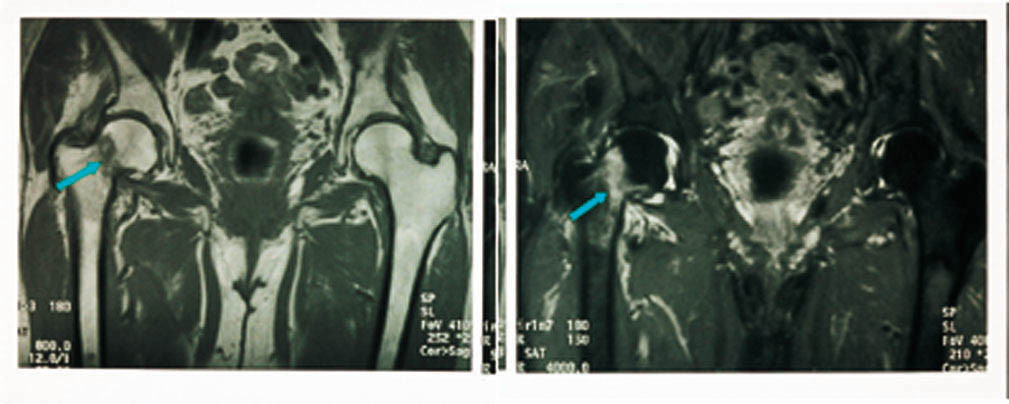

Vi har utført en MR-studie hos 27 pasienter med klinisk mistanke om collum femoris-fraktur der det var normalt eller usikkert funn ved konvensjonell røntgenundersøkelse (11). Det ble utført en koronal T1-vektet og en T2-STIR-sekvens, som til sammen tok under ti minutter. Vi fant 13 pasienter med collum femoris-fraktur eller pertrokantær fraktur, tre med bekkenringfraktur, en med acetabularfraktur, tre med muskelkontusjoner, to med beinmargsødem, to med artrose og tre normale. Vi utfører nå MR hos alle pasienter innen et døgn hvis vi er i tvil angående den konvensjonelle røntgenundersøkelsen (fig 15).